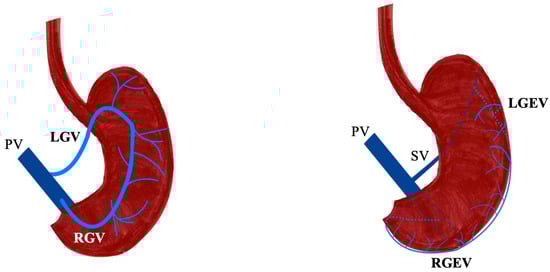

- Bruna-Mejias, A.; Salgado-Torres, C.; Cáceres-Gálvez, C.; Rodriguez-Osorio, B.; Orellana-Donoso, M.; Nova-Baeza, P.; Suazo-Santibañez, A.; Oyanedel-Amaro, G.; Sanchis-Gimeno, J.; Piagkou, M.; et al. The Gastric Vein Variants: An Evidence-Based Systematic Review of Prevalence and Clinical Considerations. J. Clin. Med. 2025, 14, 3630. [Google Scholar] [CrossRef]